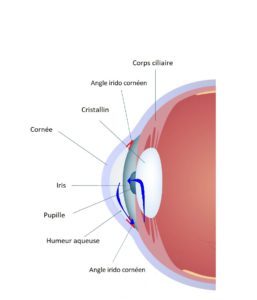

Le corps ciliaire situé juste en arrière de l’iris produit un liquide transparent nommé humeur aqueuse qui circule en avant du cristallin et de l’iris dans ce qui est appelé la chambre antérieure. L’évacuation de ce liquide se fait par l’angle irido cornéen (situé entre l’iris et la cornée) au travers d’un filtre nommé le trabéculum.

Il peut exister un obstacle au passage de l’humeur aqueuse lorsque l’iris est particulièrement dilaté (la nuit). On parle alors de glaucome par fermeture de l’angle.

Lorsqu’il n’y a aucun obstacle en amont du trabéculum mais que ce dernier présente une résistance anormalement importante au passage de l’humeur aqueuse, une élévation de la tension oculaire, apparait qui engendre le glaucome à angle ouvert.